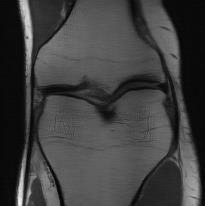

Recently, deep neural networks have greatly advanced undersampled Magnetic Resonance Image (MRI) reconstruction, wherein most studies follow the one-anatomy-one-network fashion, i.e., each expert network is trained and evaluated for a specific anatomy. Apart from inefficiency in training multiple independent models, such convention ignores the shared de-aliasing knowledge across various anatomies which can benefit each other. To explore the shared knowledge, one naive way is to combine all the data from various anatomies to train an all-round network. Unfortunately, despite the existence of the shared de-aliasing knowledge, we reveal that the exclusive knowledge across different anatomies can deteriorate specific reconstruction targets, yielding overall performance degradation. Observing this, in this study, we present a novel deep MRI reconstruction framework with both anatomy-shared and anatomy-specific parameterized learners, aiming to "seek common ground while reserving differences" across different anatomies.Particularly, the primary anatomy-shared learners are exposed to different anatomies to model flourishing shared knowledge, while the efficient anatomy-specific learners are trained with their target anatomy for exclusive knowledge. Four different implementations of anatomy-specific learners are presented and explored on the top of our framework in two MRI reconstruction networks. Comprehensive experiments on brain, knee and cardiac MRI datasets demonstrate that three of these learners are able to enhance reconstruction performance via multiple anatomy collaborative learning.